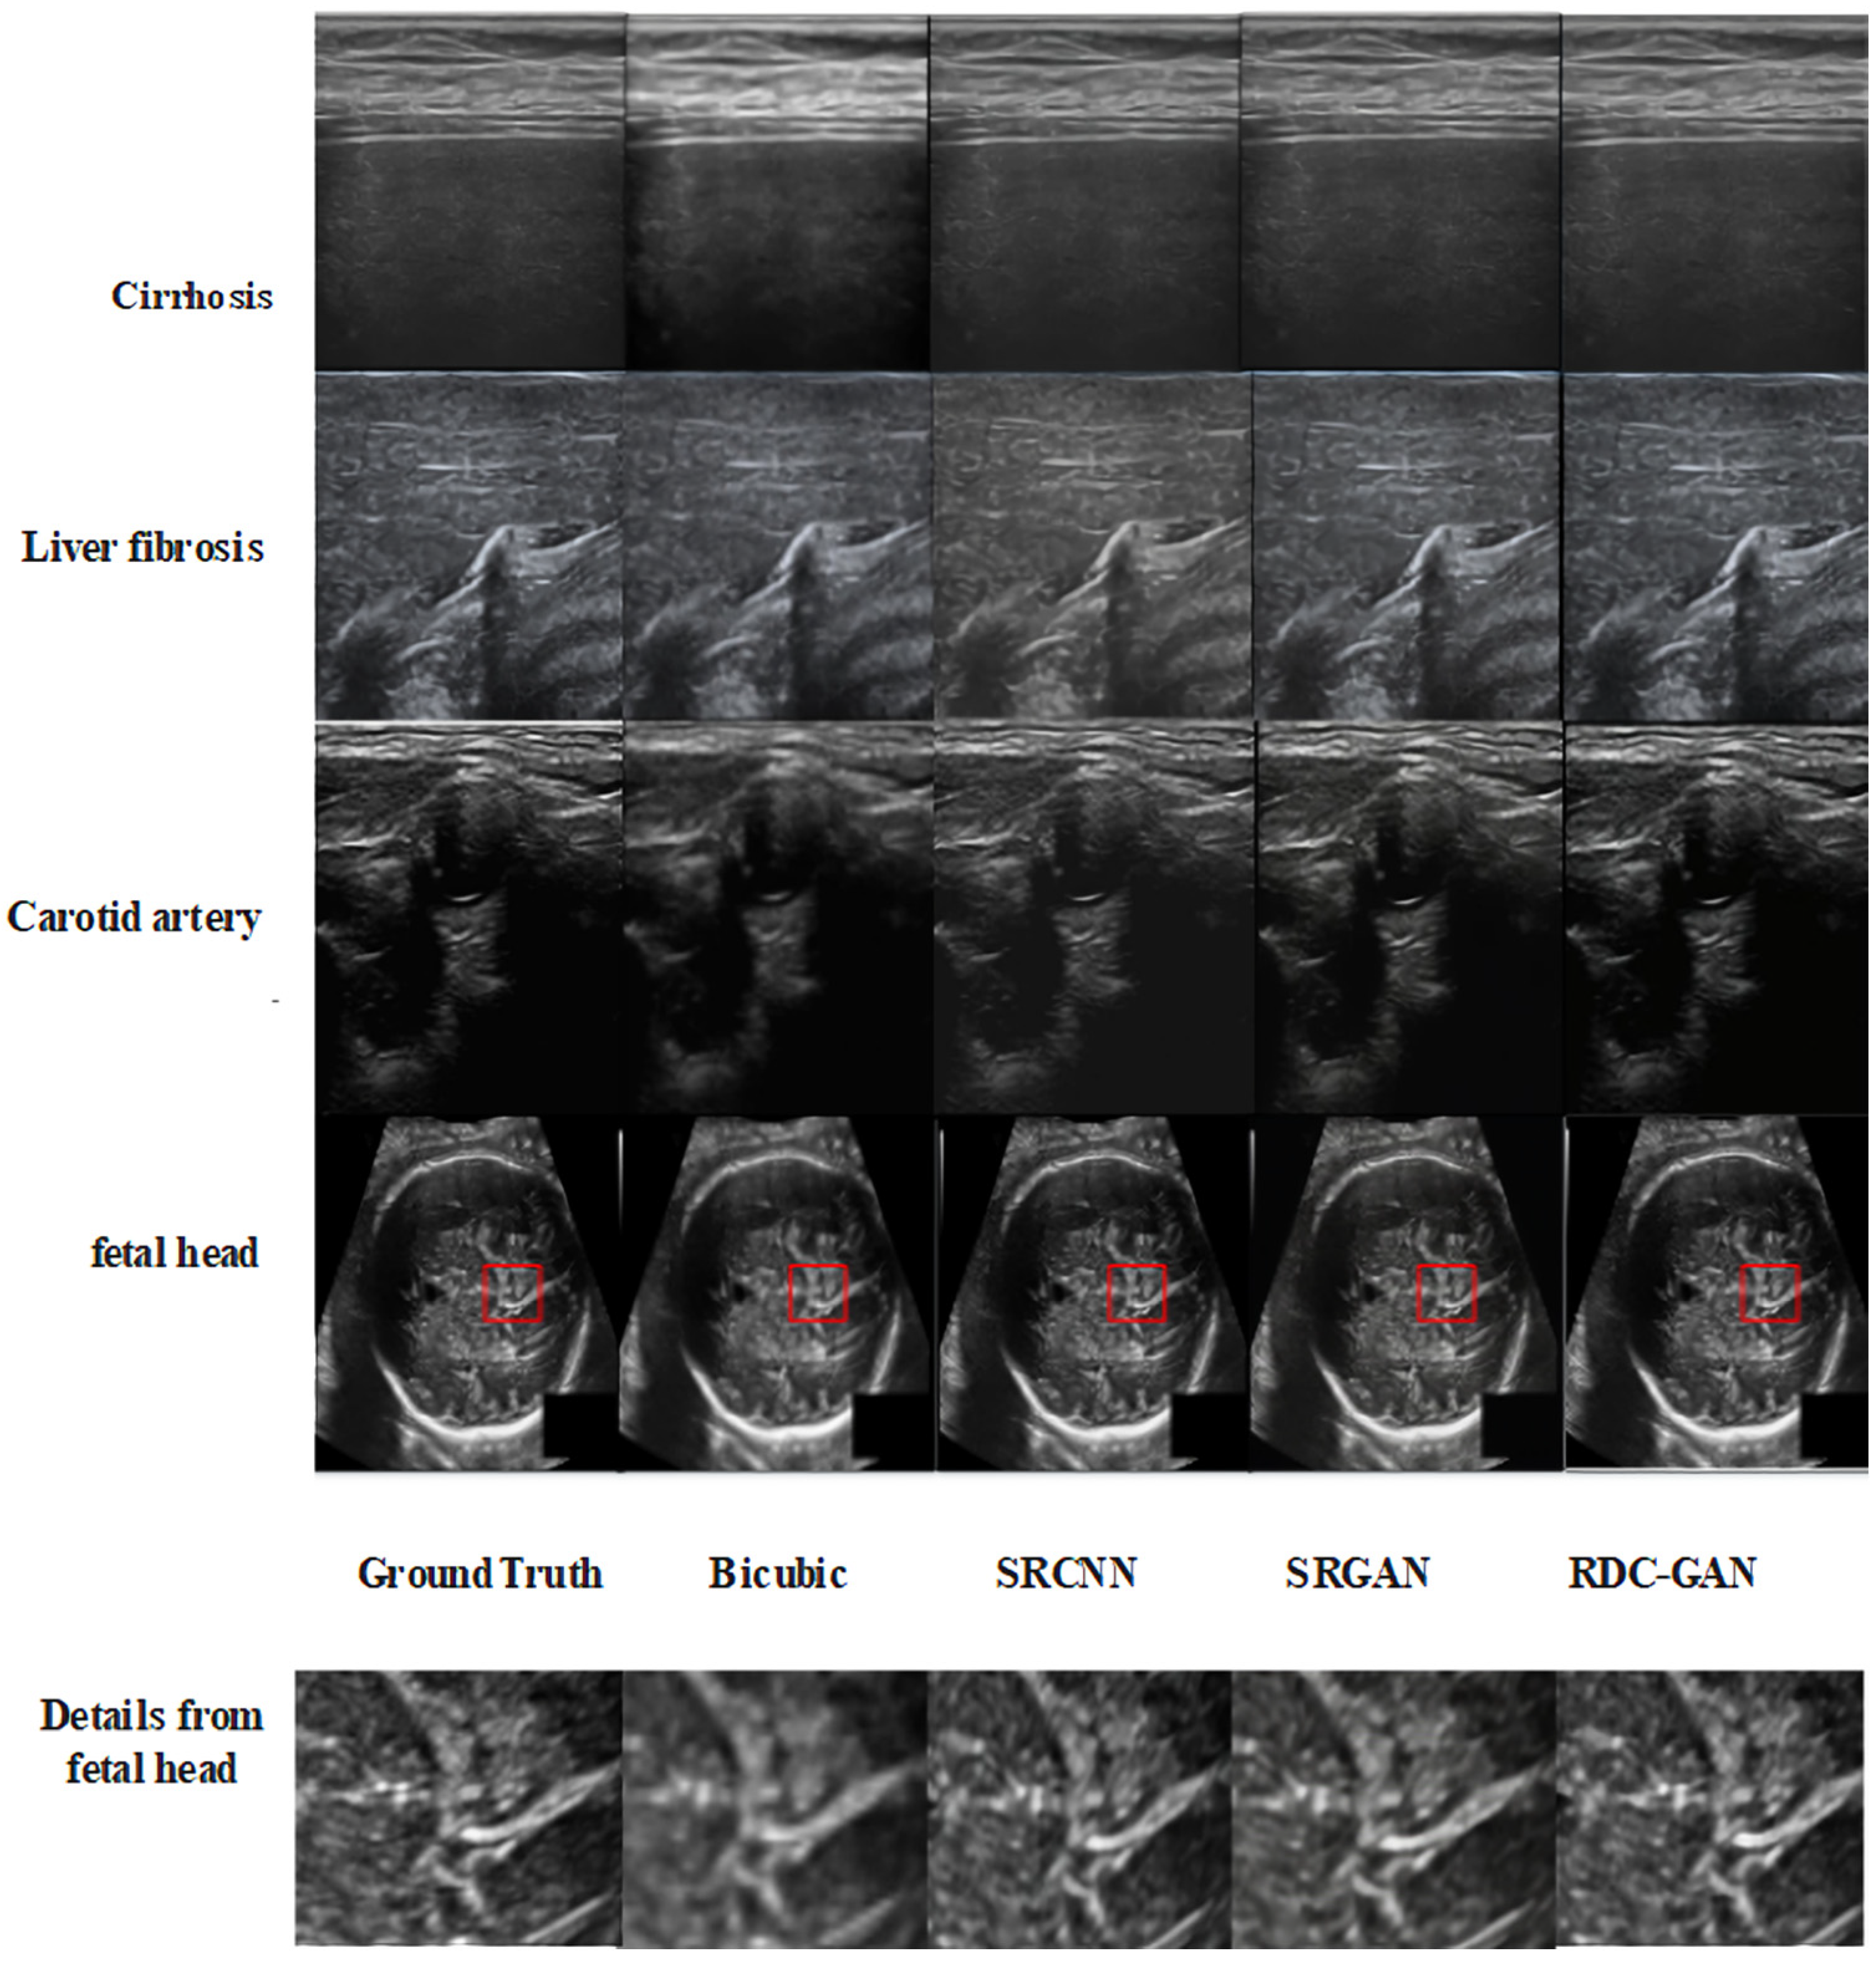

4.2. Qualitative Analysis

| Image | Algorithm | PSNR (dB) | SSIM (0–1) |

|---|---|---|---|

| Cirrhosis | Bicubic | 21.82 ± 0.06 | 0.75 ± 0.005 |

| SRCNN | 30.29 ± 0.08 | 0.84 ± 0.003 | |

| SRGAN | 25.66 ± 0.07 | 0.65 ± 0.004 | |

| RDC-GAN | 32.55 ± 0.06 | 0.88 ± 0.003 | |

| Liver fibrosis | Bicubic | 25.90 ± 0.09 | 0.80 ± 0.005 |

| SRCNN | 28.94 ± 0.06 | 0.83 ± 0.003 | |

| SRGAN | 26.09 ± 0.07 | 0.47 ± 0.004 | |

| RDC-GAN | 32.87 ± 0.06 | 0.88 ± 0.003 | |

| Carotid artery | Bicubic | 24.88 ± 0.07 | 0.83 ± 0.003 |

| SRCNN | 27.00 ± 0.08 | 0.79 ± 0.005 | |

| SRGAN | 24.57 ± 0.09 | 0.62 ± 0.003 | |

| RDC-GAN | 29.32 ± 0.06 | 0.88 ± 0.003 | |

| Fetal head | Bicubic | 25.57 ± 0.05 | 0.76 ± 0.004 |

| SRCNN | 30.86 ± 0.06 | 0.86 ± 0.004 | |

| SRGAN | 28.00 ± 0.07 | 0.58 ± 0.003 | |

| RDC-GAN | 34.11 ± 0.06 | 0.91 ± 0.003 |